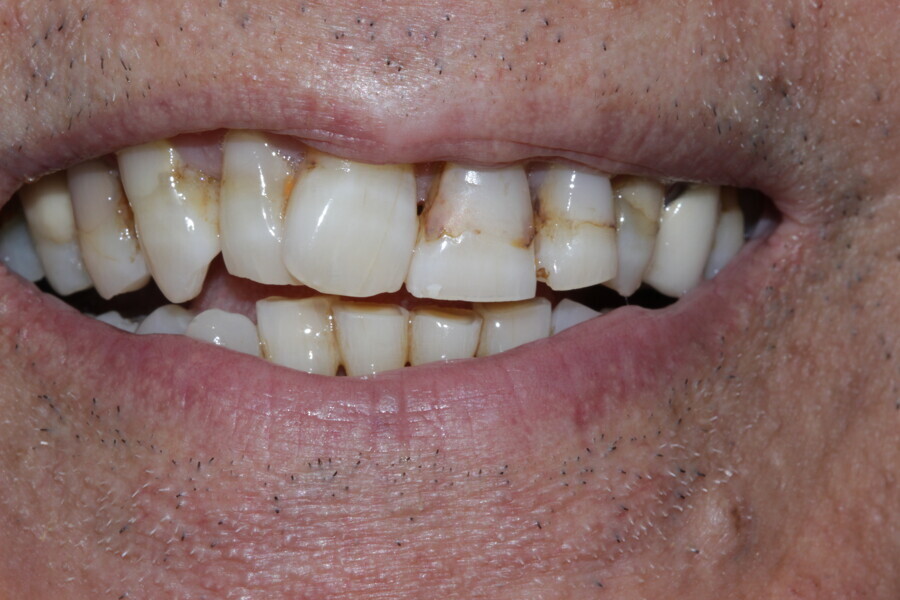

Figure 1 Close up smile before treatment